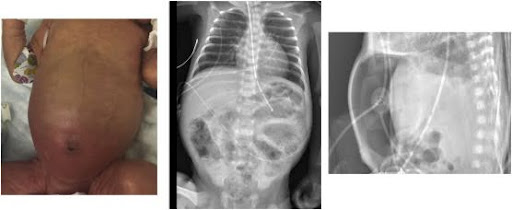

Enterocolitis is an inflammatory condition that affects your entire intestine.

Now, inflammation in one of your intestines is common, but when it happens in both, it is VERY serious.

In adults, this is a condition that requires quick medical attention because of its potential for severe complications like dehydration, sepsis, and bowel perforation…

In infants and young children, enterocolitis can be even more concerning and life-threatening.

Image Source: Science Direct

The symptoms can vary but usually include diarrhea, abdominal pain, fever, swelling and irritability.

When children get this, since young children are more vulnerable to dehydration and complications, they REALLY need immediate attention.

Histology showed patchy chronic inflammation in the colon in 11 children and reactive ileal lymphoid hyperplasia in seven, but no granulomas.